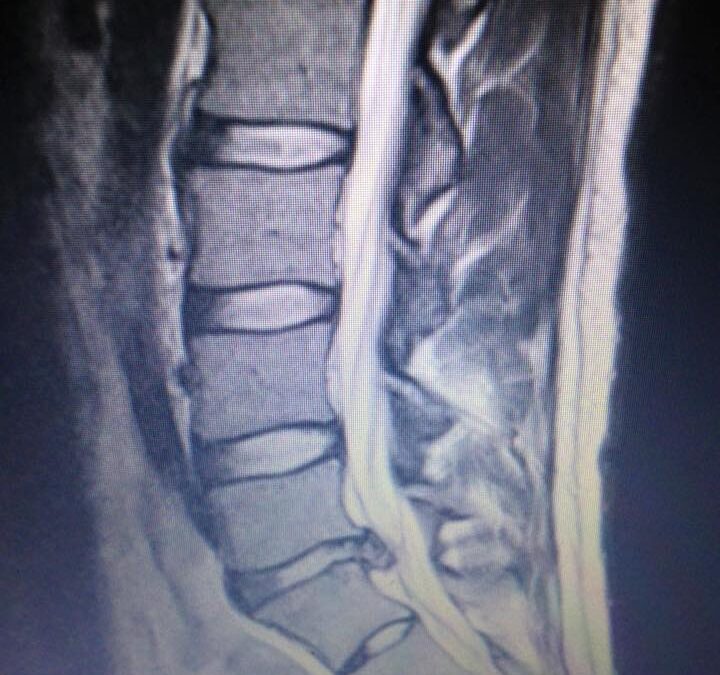

Imaging is not routine. It is considered when red flags or trauma suggest it is necessary. Examples include unrelenting night pain, progressive weakness, significant numbness, changes in bowel or bladder control, history of cancer, fever or infection risk, or recent high energy trauma. If imaging is recommended, you will know why and what the findings could change in your plan.